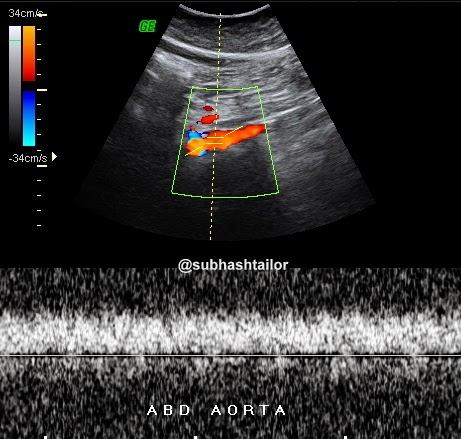

Fig 3 - Abdominal aortic doppler scan shows dampened monophasic blood flow spectrum due to low velocities , suggesting more proximal stenosis

supra-renal aorta showed a monophasic and dampened flow due to low flow

velocities [ fig 3 ], further suggesting that a more proximal narrowing is likely , &

that could be coarctation of aorta . So , a possible diagnosis of coarctation